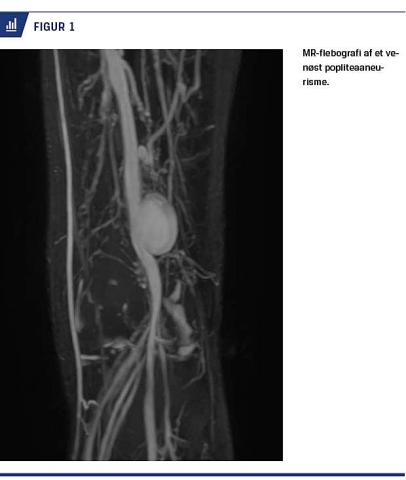

Tidligere blev diagnosen stillet ved konventionel flebografi [11, 15], men dette er i dag erstattet af farve-Doppler-UL-skanning, hvor både de anatomiske forhold og flowforhold med eventuelle tromber kan afklares. Det er dog nødvendigt, at personen, der udfører UL-skanningen, tænker på denne mulige diagnose [21, 22]. »You see what you look for, and you look for what you know« [26]. UL-skanning kan evt. suppleres med CT eller MR-flebografi (Figur 1). Det er kun sjældent, at der kan føles en udfyldning i knæhasen.